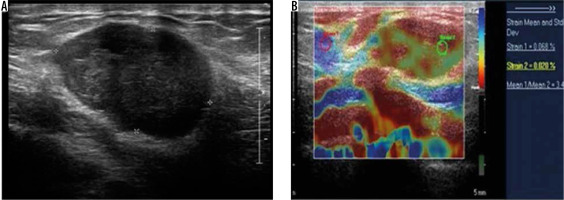

Figure 10

Subcutaneous metastases – greyscale ultrasound image (A) shows a well-defined hypoechoic lesion in the subcutaneous plane of anterior chest wall. Strain elastography (B) of the same lesion depicts it predominantly in red colour on an elastography map and a strain ratio of 3.45 suggesting the “hard” nature of the lesion and a pointer towards a malignant aetiology